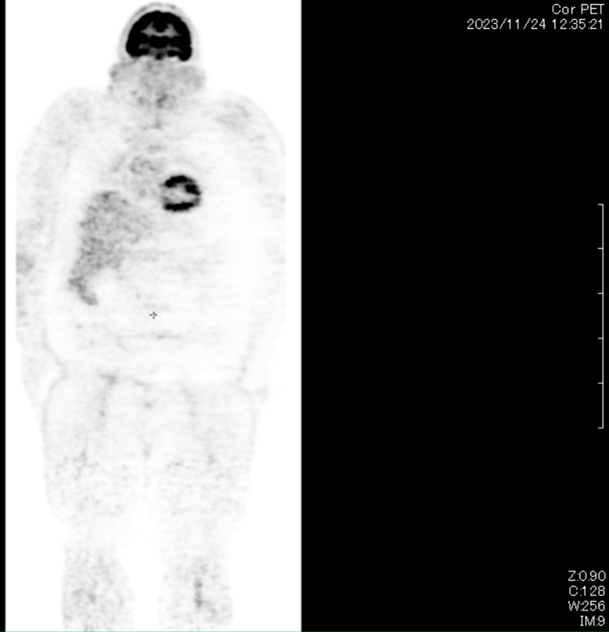

Stage IV Relapsed Colorectal Cancer with Metastasis CLEARED Cancer Patient

Mr. Alex Fassoulis, a 50 year old male from Melbourne, Australia was diagnosed with colorectal cancer in 2019. He had undergone multiple chemotherapies, radiotherapy, and surgery in Australia to control the cancer progression over three years. However, the cancer relapsed and metastasized to multiple places including his spine, ribcage, lung, and lymph nodes. The side effects of the treatment were severe and he was informed that his prospect was not promising. Not giving up, Mr. Alex searched for alternatives and found Ming through his contact of friends.

Mr. Fassoulis underwent NK cells treatment which consisted of 20 cycles of NK cells daily over a period of 4 weeks. He reported no side effects for the duration of the treatment. At the end of the cycle, Mr Fassoulis did a PET CT scan and discovered that all the tumours were cleared.